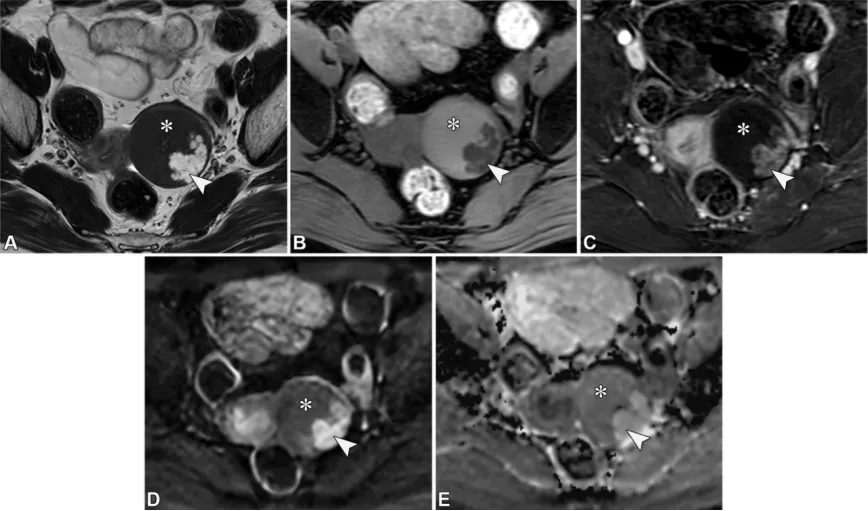

若已知存在原发性恶性肿瘤,应考虑卵巢转移瘤的可能,但卵巢转移瘤也可能是隐匿性原发性恶性肿瘤的首次表现(36)。最常见的原发部位包括结肠或子宫内膜腺癌,其次是胃、乳腺、阑尾和胰胆管腺癌。卵巢转移瘤患者通常比原发性浸润性上皮性卵巢肿瘤患者更年轻,且病变通常为双侧,生长迅速。库肯勃瘤是卵巢转移瘤的一种亚型,约占病例的50%,起源于具有分泌黏液的印戒细胞的腺癌(78)。它们通常起源于胃,但也可能源于其他部位,包括结肠、阑尾和乳腺(83)。卵巢转移瘤通常表现为双侧快速增大的实性或囊性病变,实性部分在T2加权成像上呈非低信号,在弥散加权成像上也呈非低信号。在库肯勃瘤中,囊性成分代表肿瘤细胞分泌的黏液(图33)(36,78)。

图33. 一名44岁女性患者的胃印戒细胞腺癌双侧卵巢转移(库肯勃瘤)。(A)轴位T2加权像显示右侧卵巢(RO)被带有不均质实性组织的囊性病变取代,左侧卵巢(LO)被不均质实性病变取代。右侧肿块中T2高信号的囊性部分(*)是由肿瘤细胞分泌的黏液所致。(B、C)轴位高b值扩散加权像(B)显示高信号,对应的轴位ADC图(C)显示低信号,与两个肿块中的弥散受限(箭头)一致。(D)轴位对比增强脂肪抑制T1加权像显示双侧卵巢肿块中的实性组织强化。